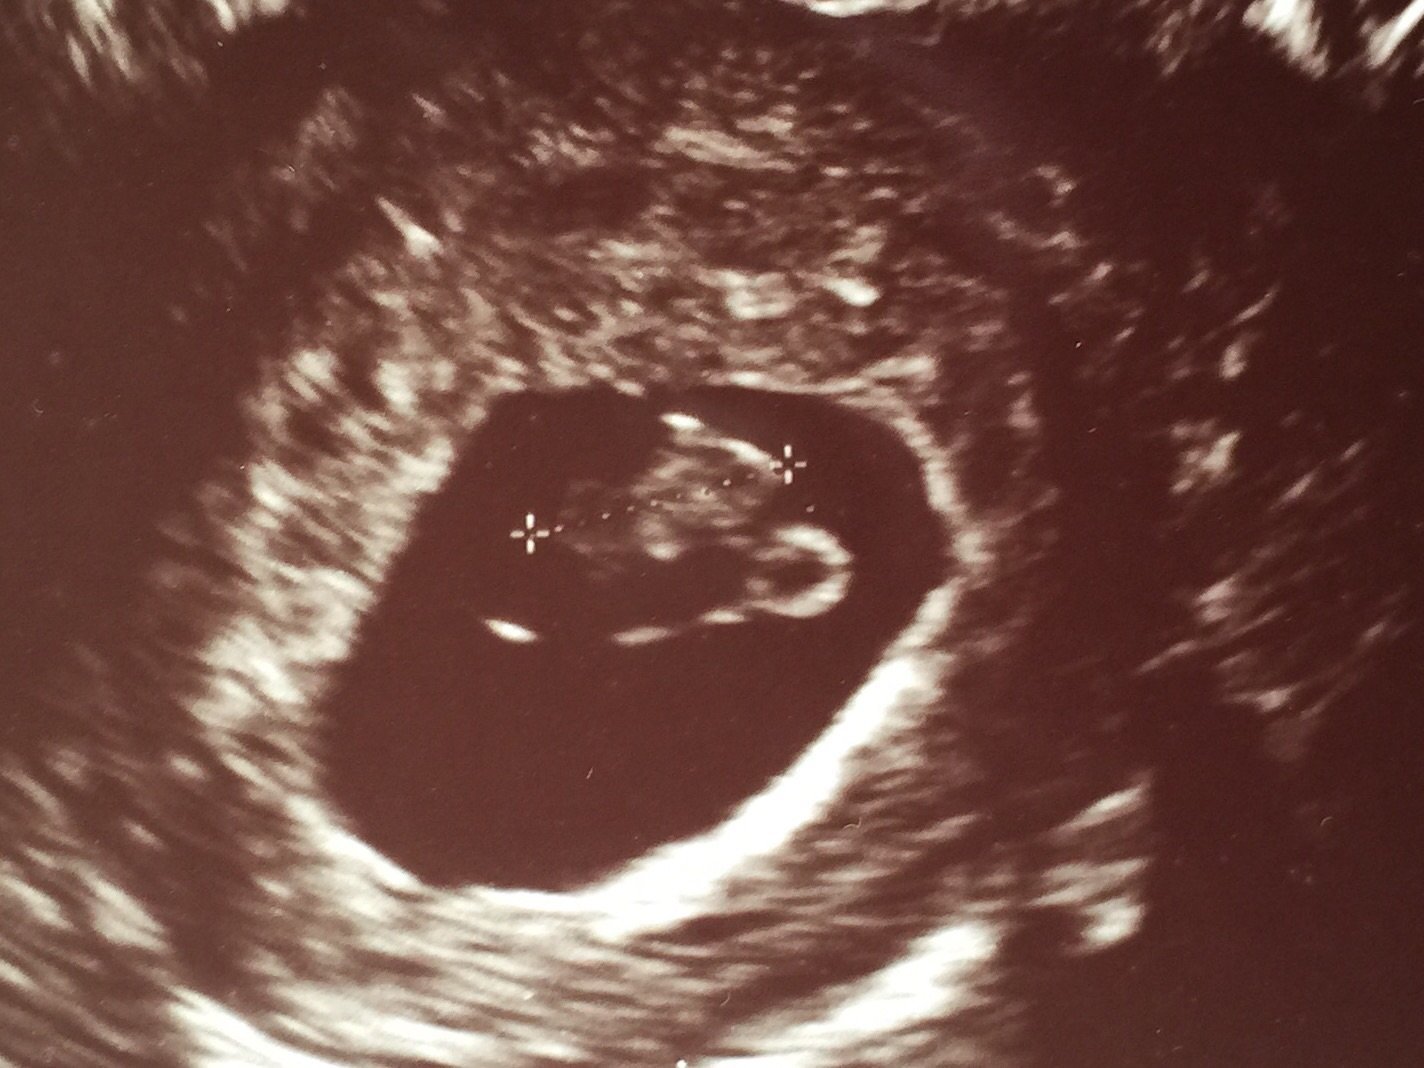

Went to the doctor's for an early ultrasound because I thought I was miscarrying. Turns out that's not quite the case! It's still early, 6 weeks 4 days, but 3 heartbeats!

Oh and it does not run in the family, and all natural conception!!